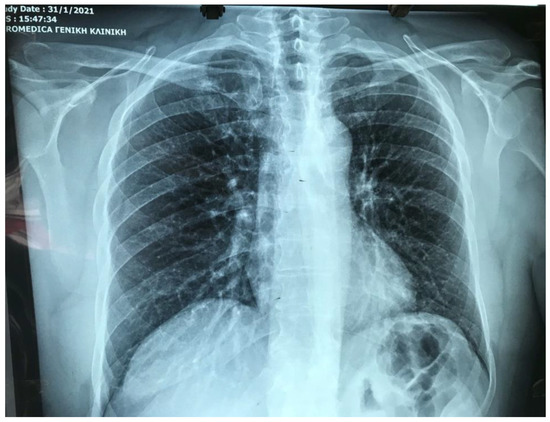

2. Case Presentation